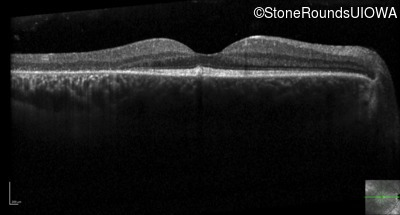

Optical Coherence Tomography - Right - 20/16

Exemplar / OCT Stack

OCT Stack